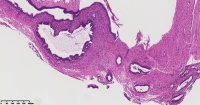

炎性息肉?潴留囊肿?腺体是否有问题?

性别

女

年龄

51岁

临床诊断

一般病史

宫颈赘生物

标本名称

图1

息肉。

稳妥起见最好做一做免疫组化。